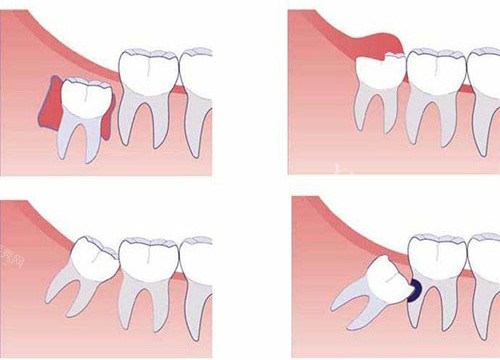

在选择口腔医院时,我做了不少功课。开封启典口腔在当地的口碑不错,尤其是他们的智齿拔除技术,让我感觉很放心。而且,他们引进了新型的小创口拔牙技术,能够在大程度上减少手术创伤,缩短改善时间。这对于害怕拔牙的我来说,无疑是大的安慰。

医生为我拍了X光片,仔细查看了我的智齿情况。原来,我的智齿是横向阻生的,难怪会这么疼。医生耐心地向我解释了智齿的位置和拔除的必要性,并制定了详细的手术方案。